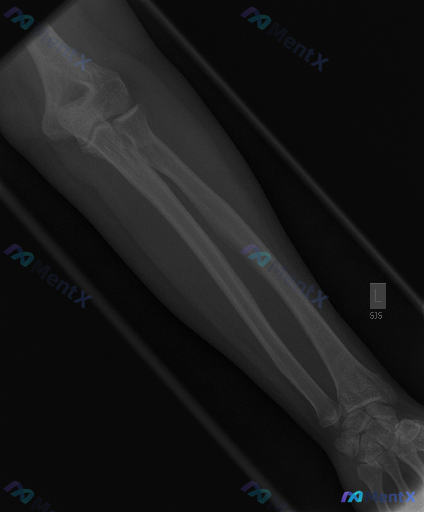

基本背景:影像显示为青少年骨骼发育阶段(存在骨骺生长板)。

影像表现(左前臂正位X光):

- 尺桡骨皮质连续,未见明确骨折线、脱位或半脱位;

- 各关节间隙宽度尚可,关节面平整;

- 前臂软组织轮廓清晰,未见明显弥漫肿胀、脂肪垫征或异物/钙化影;

- 整体骨密度均匀,未见骨膜反应、骨质破坏或软组织肿块。

临床判断前提:结合临床背景,仍考虑「存在异常」。